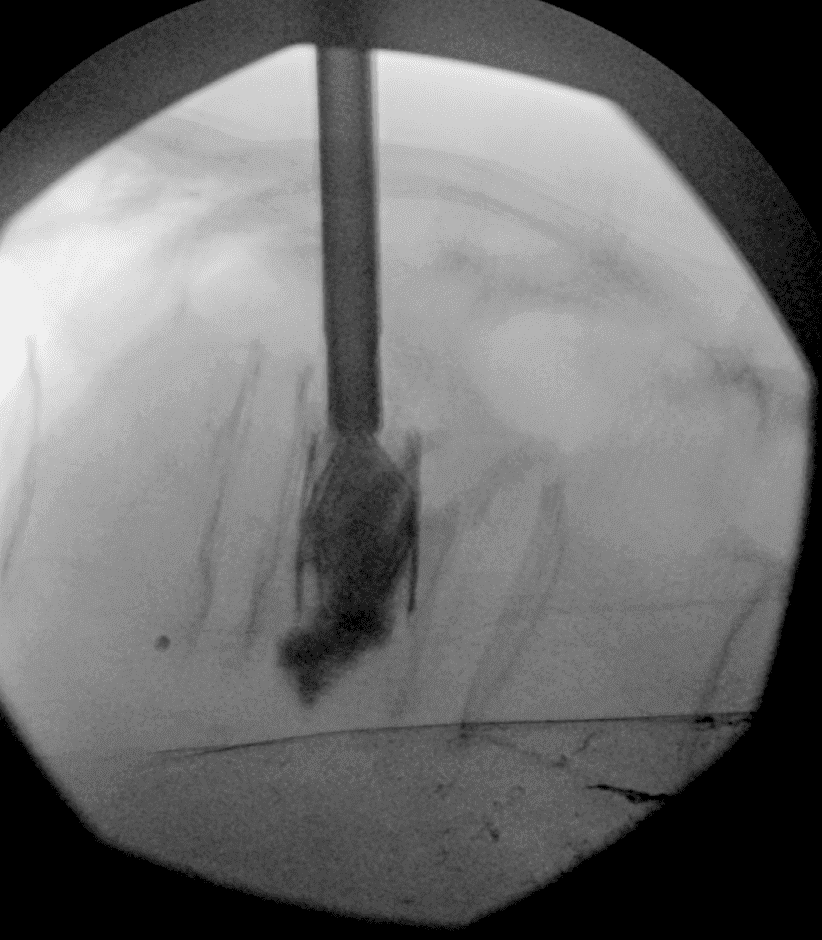

Insertion et déploiement de l’implant

L’implant SPINEJACK est introduit dans le corps vertébral. Une fois en place, il est progressivement déployé pour redresser la vertèbre et restaurer sa hauteur, améliorant ainsi la posture et réduisant la douleur.

Guidage par imagerie

À l’aide de la fluoroscopie et/ou du scanner, l’équipe médicale guide avec précision une aiguille jusqu’au site de la fracture, en s’assurant d’éviter les structures sensibles.